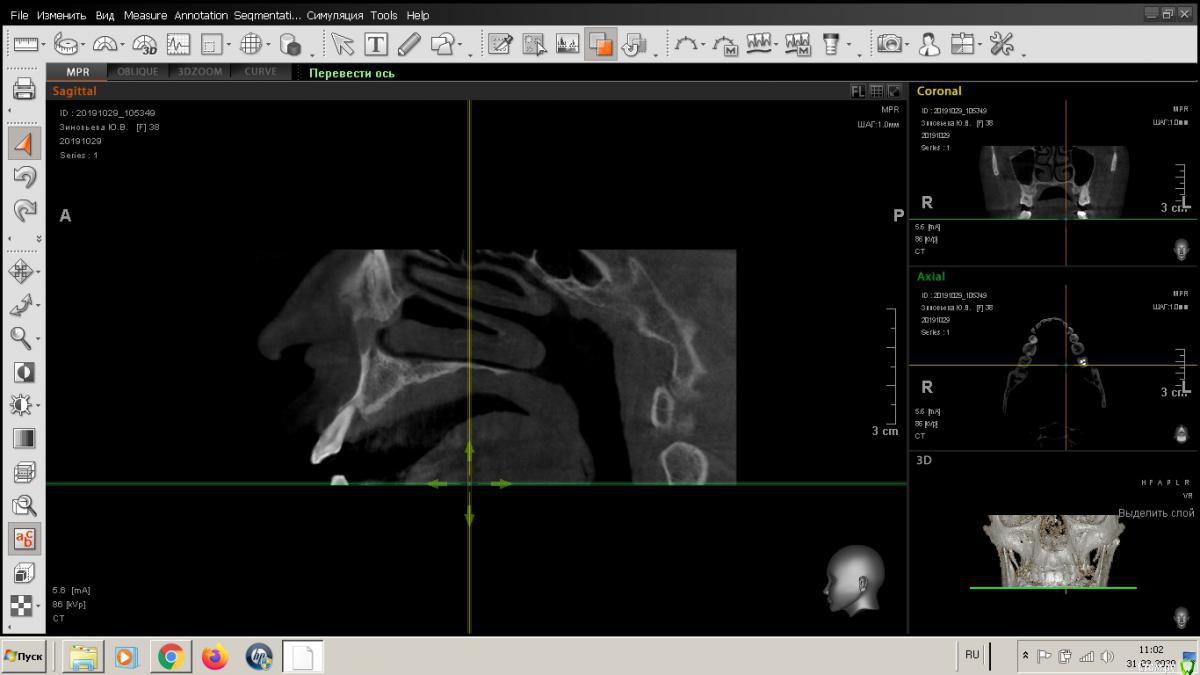

Любстер Опубликовано 31 марта, 2020 Поделиться Опубликовано 31 марта, 2020 Обратилась в октябре 2019 пациентка с жалобами на подвижность 22 зуба. Мы были третьей клиникой, куда она обратилась, везде ей говорили, что зуб сохранить нельзя, но... Также пациентка заявила, что очень боится врачей, хватает их за руки, ведет себя неадекватно, требовала общую анестезию. Мы ей рекомендовали обратиться в клинику, которая работает с анестезиологами, благополучно распрощались и забыли. И тут она опять пришла, на зубе 21 фиксирована циркониевая коронка, которую этот шатающийся 22 выдавил неведомым образом. Она эту коронку самостоятельно фиксирует обратно и так ходит. И еще она узнала, сколько стоит с общим обезболиванием процедура и решила, что лучше вернется к нам. В общем, я думаю, что с ней делать, сделать по типу консервации лунки или полноценную костную пластику с отслаиванием лоскута. Подскажите, как вы в таких случаях действуете?Записана на завтра, настаивает на операции, хотя ей было доведено, что только экстренные случаи. Я хочу от нее откреститься, главный врач говорит принять по заявлению от нее, что считает свой случай экстренным. Ссылка на комментарий

Любстер Опубликовано 31 марта, 2020 Автор Поделиться Опубликовано 31 марта, 2020 Я бы просто удалила дальше? пациентка хочет имплантацию, а кости нет, судя по кт Ссылка на комментарий